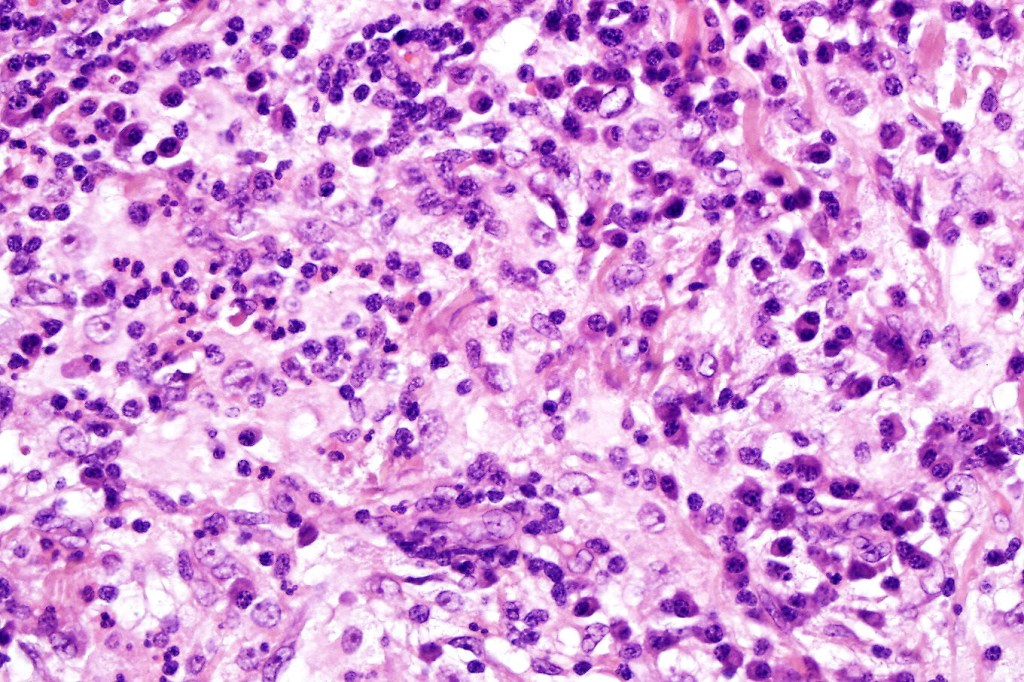

•Due to the admixture of pale histiocytes and lymphocytes, the scanning view is characteristic, and the diagnosis can be strongly suspected at this magnification

•Dense dermal nodular infiltrate sometimes extending into subcutaneous fat

•Histiocytes are large with irregular borders and abundant cytoplasm

• Vesicular nuclei with a prominent nucleoli

•Emperipolesis of lymphocytes, plasma cells & neutrophils

•Background population of lymphocytes, plasma cells, neutrophils, eosinophils & variable numbers of xanthoma cells

•Lymphoid follicles with germinal centers sometimes present

•Fibrosis is occasionally conspicuous